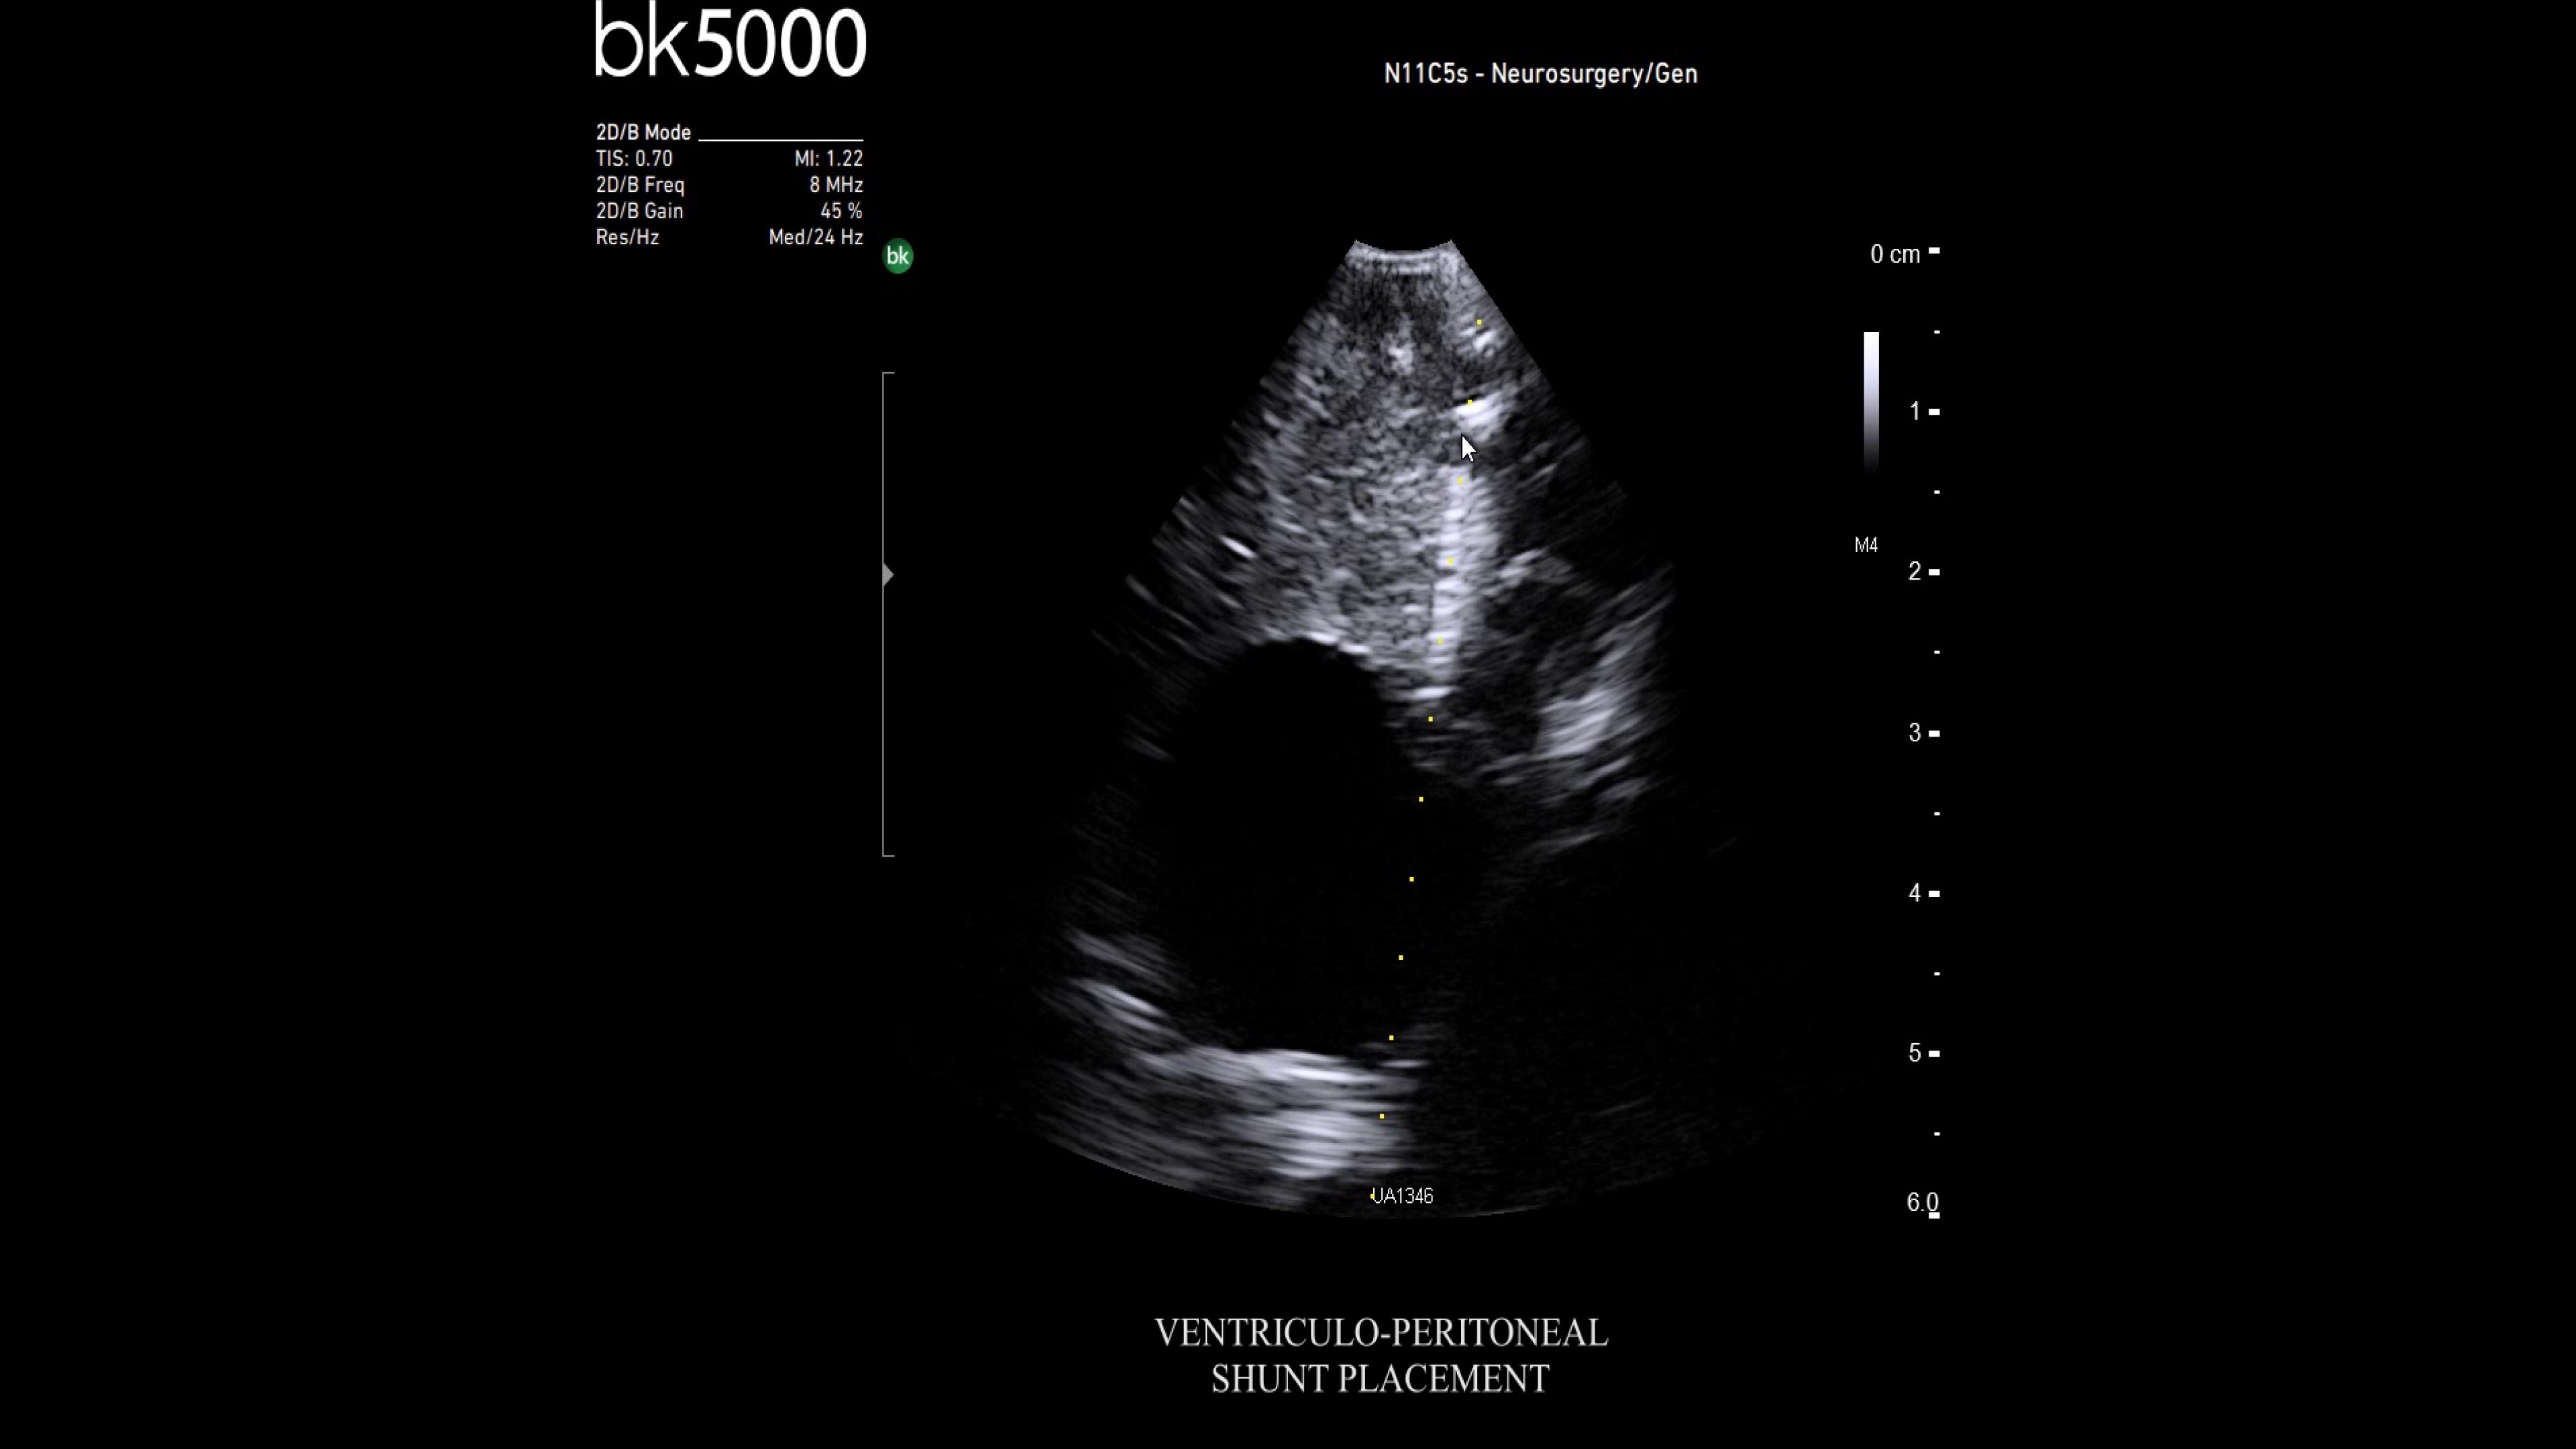

Ultrasound enhances neurosurgery by providing real-time navigation and lesion identification, crucial as preoperative CT/MRI data can be outdated. The bk5000 system offers high-quality images to see lesion margins and determine actions. Advanced graphics processing ensures immediate, auto-optimized images.

• Neurosurgery transducers: High-resolution, sterilizable transducers provide detailed brain and spinal cord images. The Smart™ button allows easy activation, freezing, storing, or printing of images. Disposable needle guides aid lesion targeting.

• Digital integration with Brainlab: Brainlab software offers real-time ultrasound overlay on pre-op MRI/CT, showing brain shift instantly. It scans and reconstructs 3D ultrasound data faster than intraoperative MR/CT, with no image quality loss.